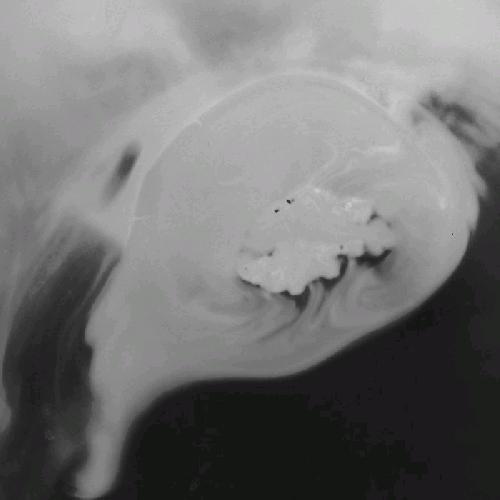

Cat Soup (PT)

Cat Soup